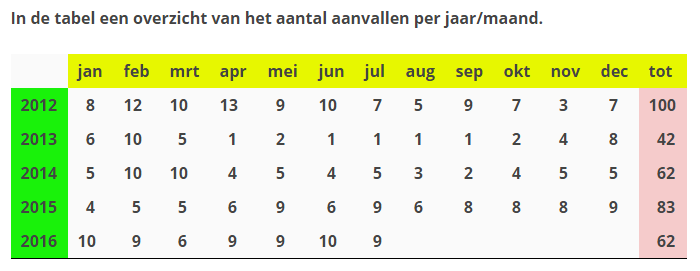

In een periode van vijf jaar werden er door de kno-artsen van het MCL te Leeuwarden een aantal misdiagnoses bij mij vastgesteld m.b.t. mijn evenwichtsstoornissen.. In de eerste plaats dachten ze aan de Ziekte van Ménière en later BPPV. Helaas bleek dit niet de juiste diagnoses te zijn, ondanks de vele onderzoeken en oefeningen die ik moest ondergaan. Het werd eerder slechter dan beter. Ik vroeg mij ook wel eens af of de betreffende medici wel interesse hebben in de voortgang op hun vakgebied. Eigenlijk hoeft het niet voor hun, want de wachtkamers zitten toch altijd vol. Helaas worden de patiënten de dupe, net zoals ik mee heb gemaakt. In totaal heb ik 362 (225 lichte en 137 zware) evenwichtsstoornissen gehad.

Ik liet hem ook mijn overzicht zien waarop ik bijhoud hoe vaak ik een evenwichtsstoornis heb gehad. Deze waren drastisch afgenomen sinds ik het medicijn Carbamazepine gebruik. Ik gebruik nu twee tabletten per dag (totaal 400 Mg). Dit was een bevestiging voor de Professor dat hij toen de juiste diagnose heeft gesteld en het ziet er veelbelovend uit. Vol trots liet hij het overzicht van mij aan zijn collega dr. Vincent van Rompaey zien. Zij waren beiden even in een juich stemming. Vervolgens heeft Floris nog een gesloten bril op mijn neus gezet en mij in verschillende houdingen gezet, waarbij hij op een scherm kon zien hoe mijn ogen daarop reageren. Daar kwamen geen noemenswaardige dingen uit.

Op dit moment gaat het wel weer redelijk goed en zijn de aanvallen afgenomen. Ik heb de afgelopen periode van 4 weken maar 1 aanval gehad (vorig jaar in dezelfde periode 8). Die ene aanval werd veroorzaakt op een schoolplein waar het een drukte van belang was en de moeders die hun kroost ophalen geen oog voor je hebben en mij bijna omver liepen. Of liep ik ze omver, ik weet het niet meer…..

Het is enige tijd stil geweest op deze blog. Niet dat er niets gebeurt is….De stand van zaken omtrent mijn evenwichtsstoornis (ziekte van Ménière) is dat ik er nog steeds last van heb. In de grafiek is te zien de aanvallen over de afgelopen 3 jaar.

De gelopen periode zijn er weer een aantal onderzoeken geweest m.b.t. mijn evenwichtsstoornissen. Ik ben nu onder behandeling van het UMCG. Het afgelopen jaar (2012) heb ik 100 evenwichtsstoornissen gehad. Dat varieerde van kleine tot grote “aanvallen”. En het gaat gewoon door, want deze maand heb ik alweer 5 aanvallen gehad.